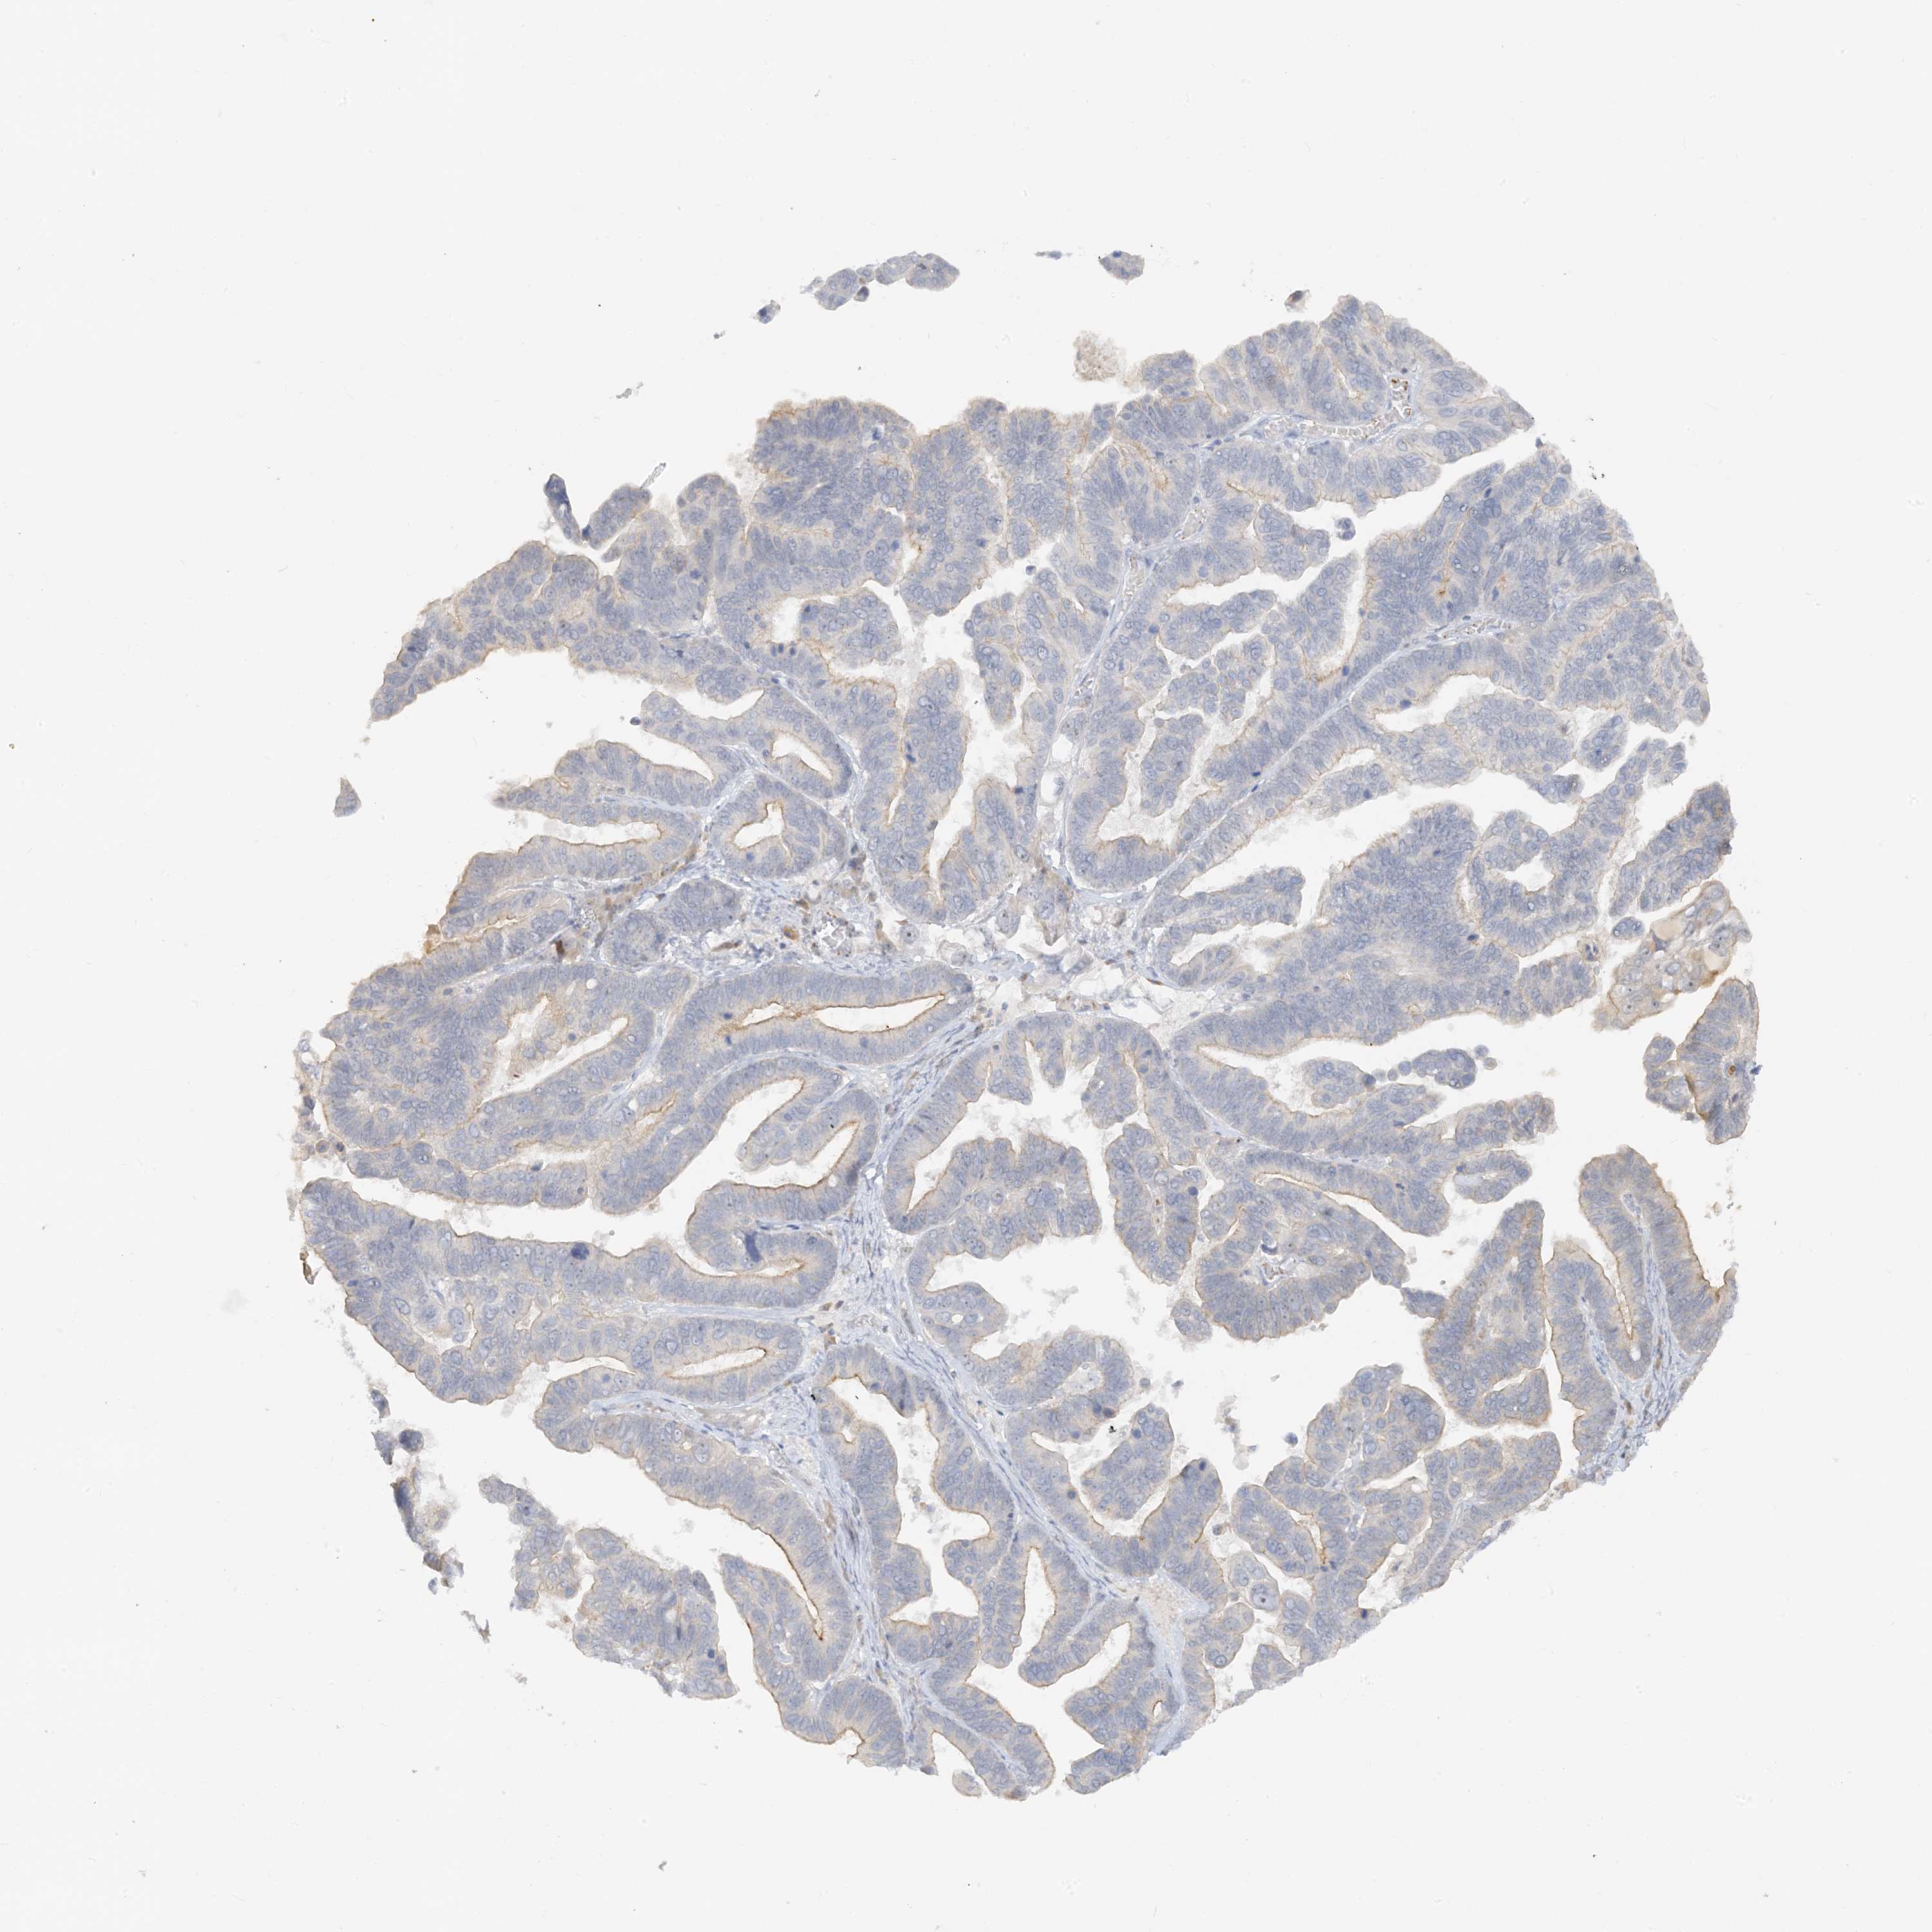

OVARIAN CANCER - Protein expressioni

A mouse-over function shows sample information and annotation data. Click on an image to view it in a full screen mode. Samples can be filtered based on level of antibody staining by selecting one or several of the following categories: high, medium, low and not detected. The assay and annotation is described here.

Note that samples used for immunohistochemistry by the Human Protein Atlas do not correspond to samples in the TCGA dataset.

Antibody stainingi

Antibody staining in the annotated cell types in the current human tissue is reported as not detected, low, medium, or high, based on conventional immunohistochemistry profiling in selected tissues. This score is based on the combination of the staining intensity and fraction of stained cells.

Each image is clickable and will lead to virtual microscopy that enables deeper exploration of all samples and also displays staining intensity scores, fraction scores and subcellular localization as well as patient and tissue information for each sample.

Antibody HPA035048

Antibody HPA035049

Carcinoma, endometroid